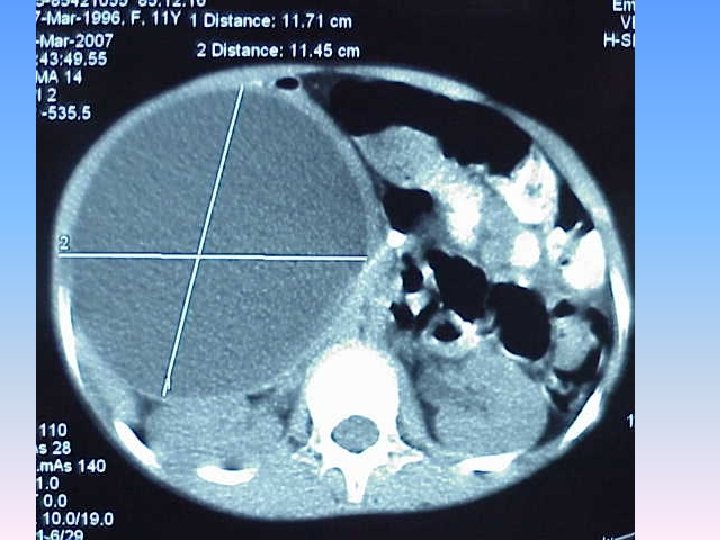

Abdominal CT Scan § A regular lobulated cystic mass in right lobe of liver (120 x 120) without calcification causing dilatation of intra & extra biliary ducts.